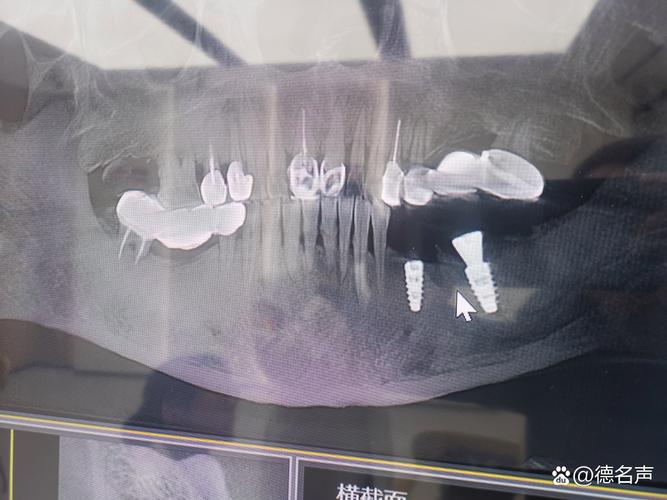

- 骨量(高度和宽度): 种植体需要植入足够的骨组织中才能稳固,X光(尤其是全景片和CBCT)能精确测量牙槽骨的高度、宽度和密度,判断是否足够容纳种植体。

- 下牙槽神经管: 在下颌后牙区,种植体必须避开下牙槽神经,否则会导致下唇、下巴麻木甚至永久性损伤,X光能清晰显示神经管的位置和走向。

- 上颌窦: 在上颌后牙区,种植体不能穿入上颌窦,X光能显示上颌窦底的位置、大小和形态,帮助医生确定种植体植入的安全深度和位置。

- 邻牙牙根: 确保种植体不会损伤邻牙的牙根。

(图片来源网络,侵删)检查邻牙、对颌牙是否有蛀牙、牙周病、根尖病变等问题,这些都需要在种植前或同时进行治疗。